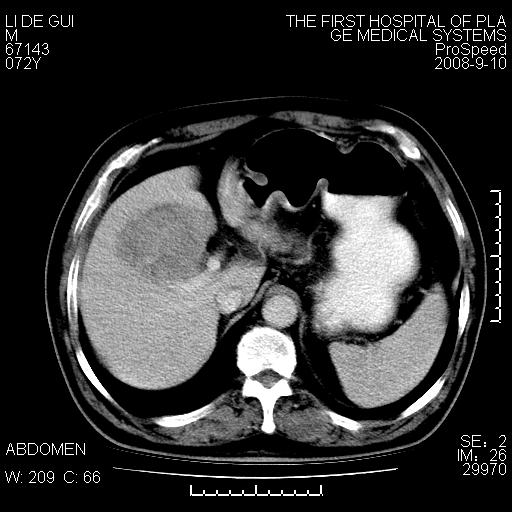

标题: CT17988:腹部肿块两年,肿块大小无变化,患者无不适,自我 [打印本页]

标题: CT17988:腹部肿块两年,肿块大小无变化,患者无不适,自我

胆囊占位性病变(黄色肉芽肿性胆囊炎?)。

考虑-----胆囊血肿机化或胆囊癌或腺肌增生症------增强

十二指肠的间质瘤